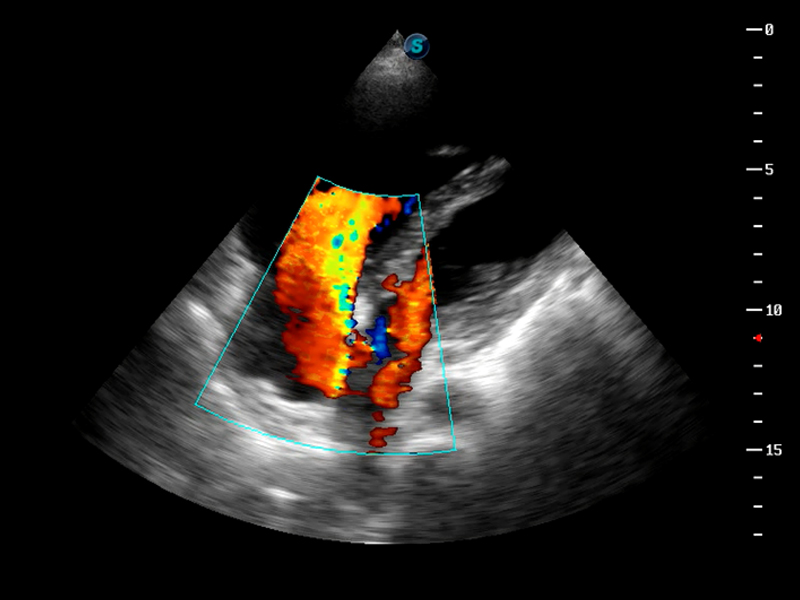

μ-Scan微米成像

AutoC智能血流追踪